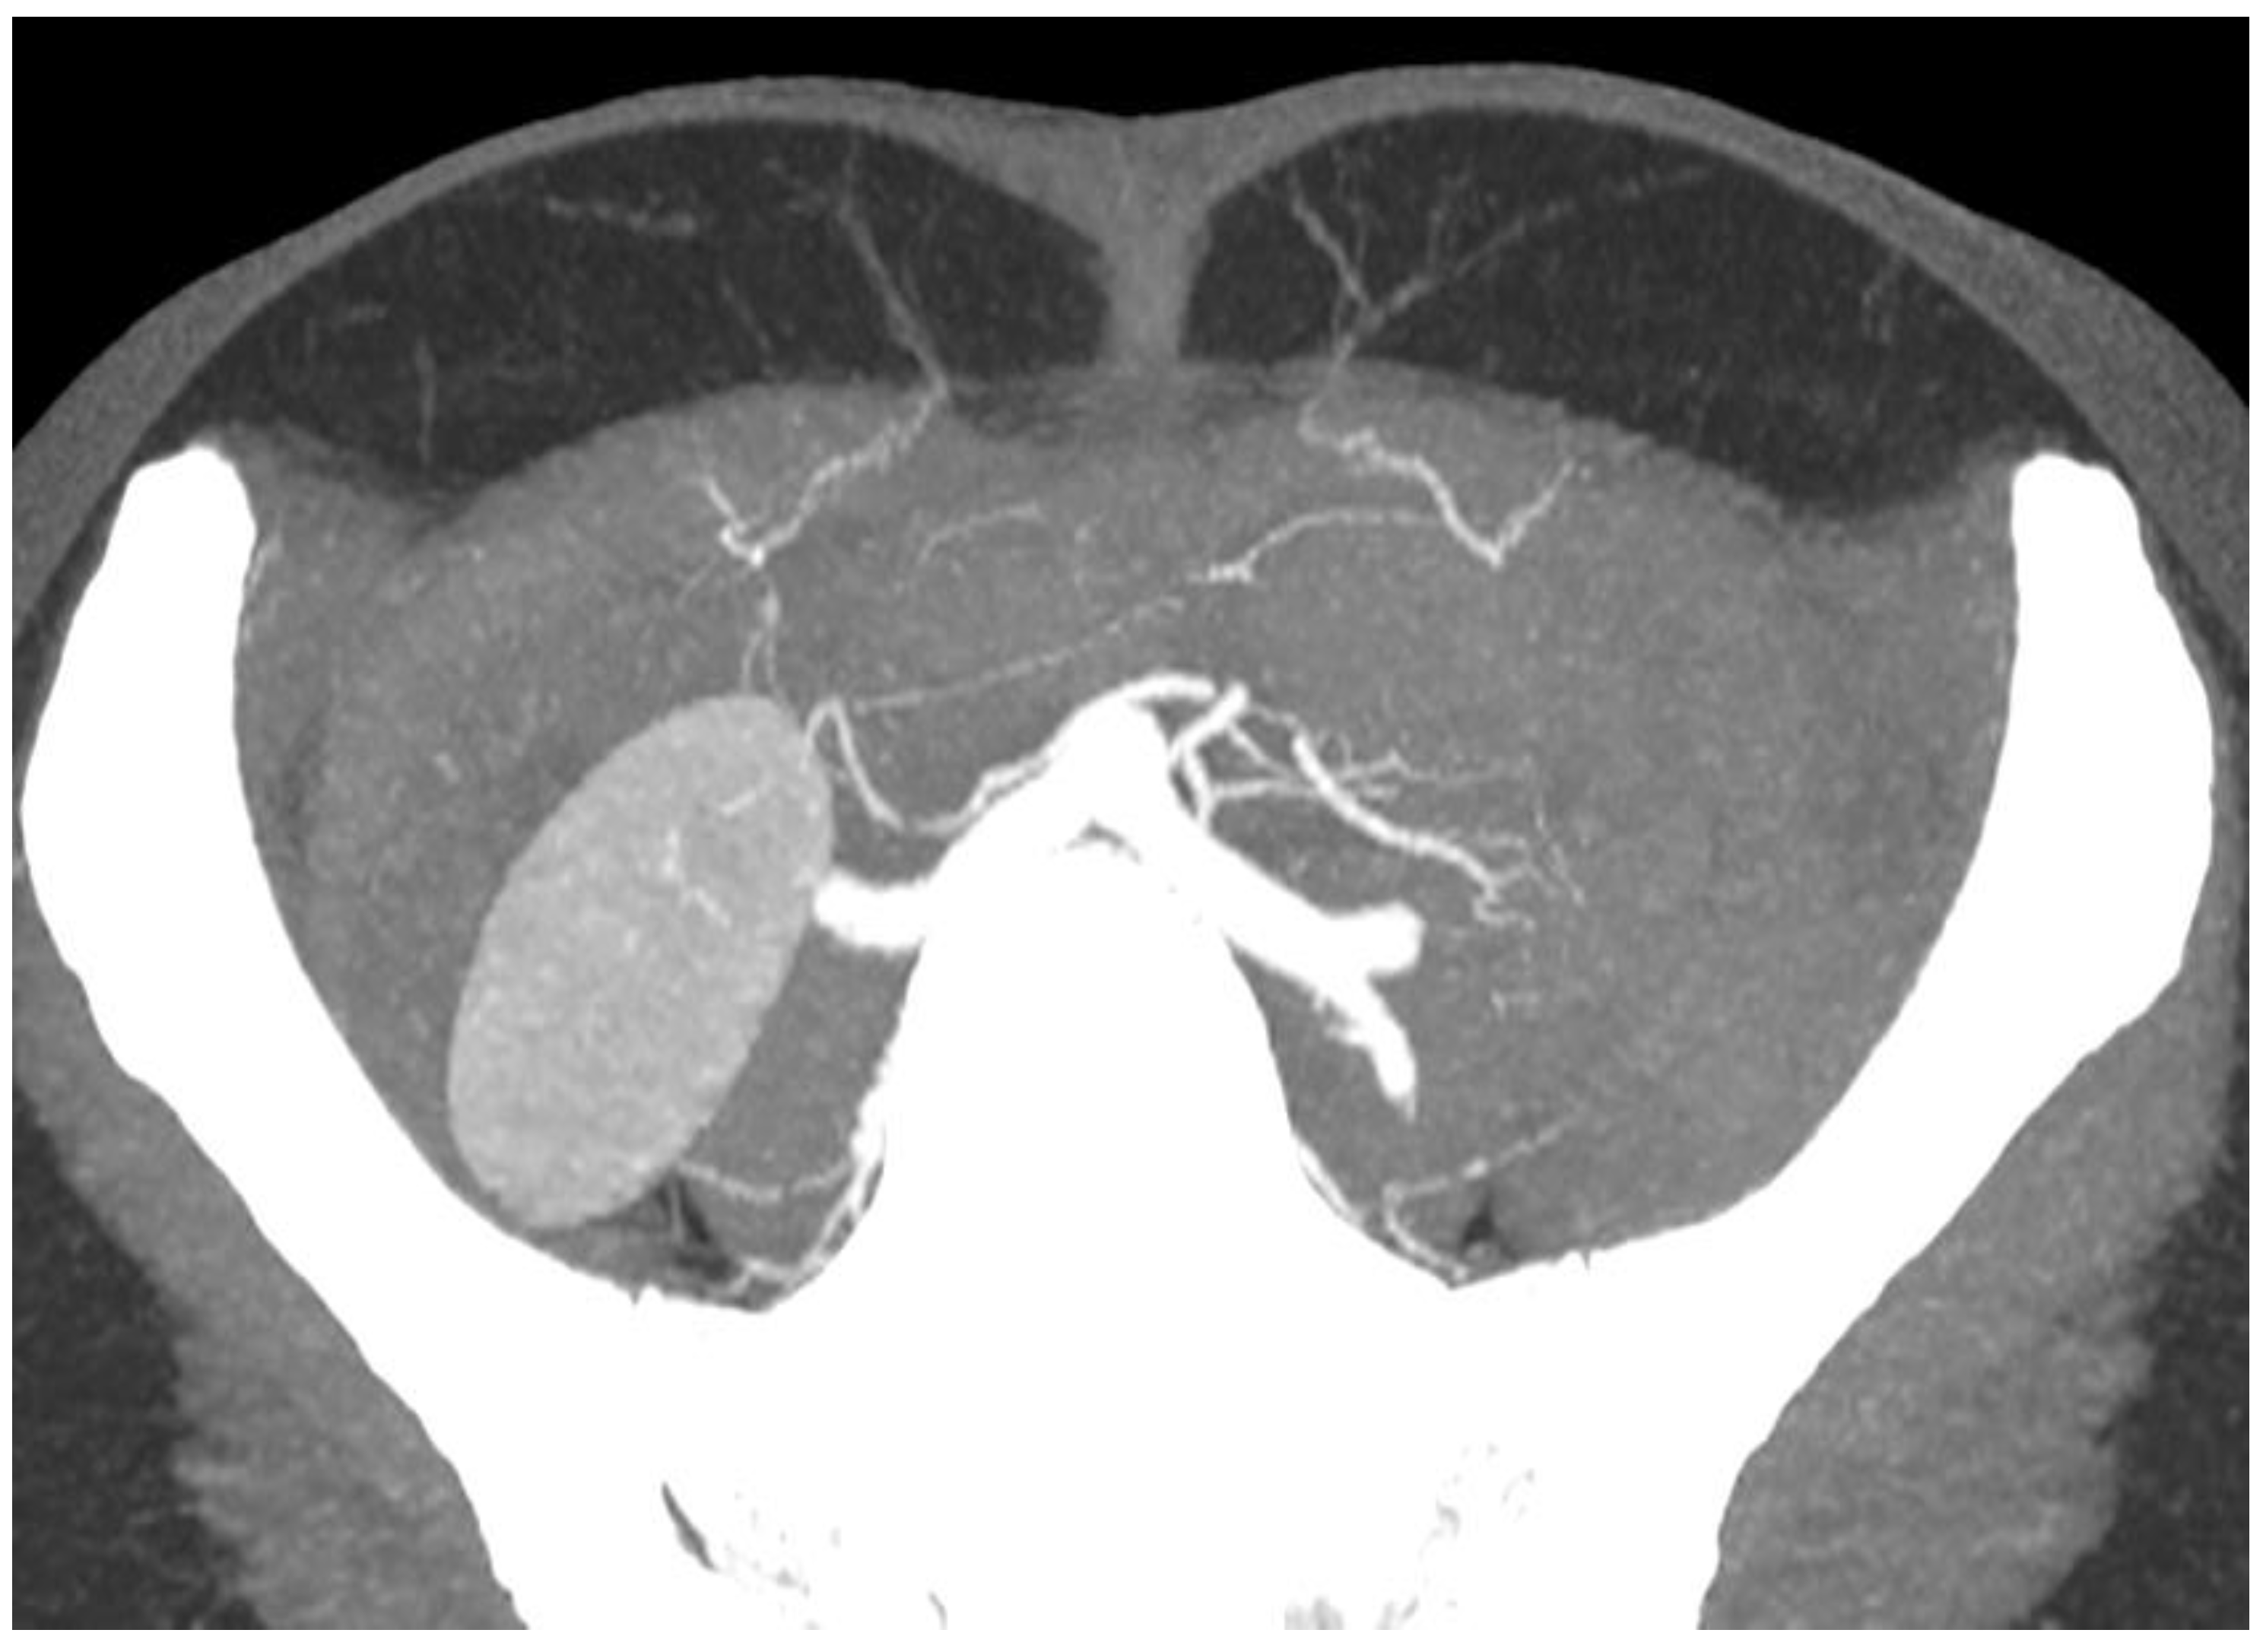

- Rozen, W.M.; Bhullar, H.K.; Hunter-Smith, D. How to assess a CTA of the abdomen to plan an autologous breast reconstruction. Gland Surg. 2019, 8, S291–S296. [Google Scholar] [CrossRef]

- Masia, J.; Clavero, J.A.; Larrañaga, J.R.; Alomar, X.; Pons, G.; Serret, P. Multidetector-row computed tomography in the planning of abdominal perforator flaps. J. Plast. Reconstr. Aesthet. Surg. 2006, 59, 594–599. [Google Scholar] [CrossRef] [PubMed]

- Rozen, W.M.; Phillips, T.J.; Ashton, M.W.; Stella, D.L.; Taylor, G.I. A new preoperative imaging modality for free flaps in breast reconstruction: Computed tomographic angiography. Plast. Reconstr. Surg. 2008, 122, 38e–40e. [Google Scholar] [CrossRef]

- Mihara, M.; Nakanishi, M.; Nakashima, M.; Narushima, M.; Koshima, I. Utility and anatomical examination of the DIEP flap’s three-dimensional image with multidetector computed tomography. Plast. Reconstr. Surg. 2008, 122, 40e–41e. [Google Scholar] [CrossRef]

- Alonso-Burgos, A.; García-Tutor, E.; Bastarrika, G.; Cano, D.; Martínez-Cuesta, A.; Pina, L.J. Preoperative planning of deep inferior epigastric artery perforator flap reconstruction with multislice-CT angiography: Imaging findings and initial experience. J. Plast. Reconstr. Aesthet. Surg. 2006, 59, 585–593. [Google Scholar] [CrossRef]

- Cevik, J.; Rozen, W. A Novel optimization technique of Computed Tomography Angiographic 3D-reconstructions for pre-operative planning of DIEP flaps. JPRAS Open 2023, 35, 38–41. [Google Scholar] [CrossRef]

- Fitzgerald O’Connor, E.; Rozen, W.M.; Chowdhry, M.; Band, B.; Ramakrishnan, V.V.; Griffiths, M. Preoperative computed tomography angiography for planning DIEP flap breast reconstruction reduces operative time and overall complications. Gland Surg. 2016, 5, 93–98. [Google Scholar] [CrossRef]

- Rozen, W.M.; Ashton, M.W.; Grinsell, D.; Stella, D.L.; Phillips, T.J.; Taylor, G.I. Establishing the case for CT angiography in the preoperative imaging of abdominal wall perforators. Microsurgery 2008, 28, 306–313. [Google Scholar] [CrossRef] [PubMed]